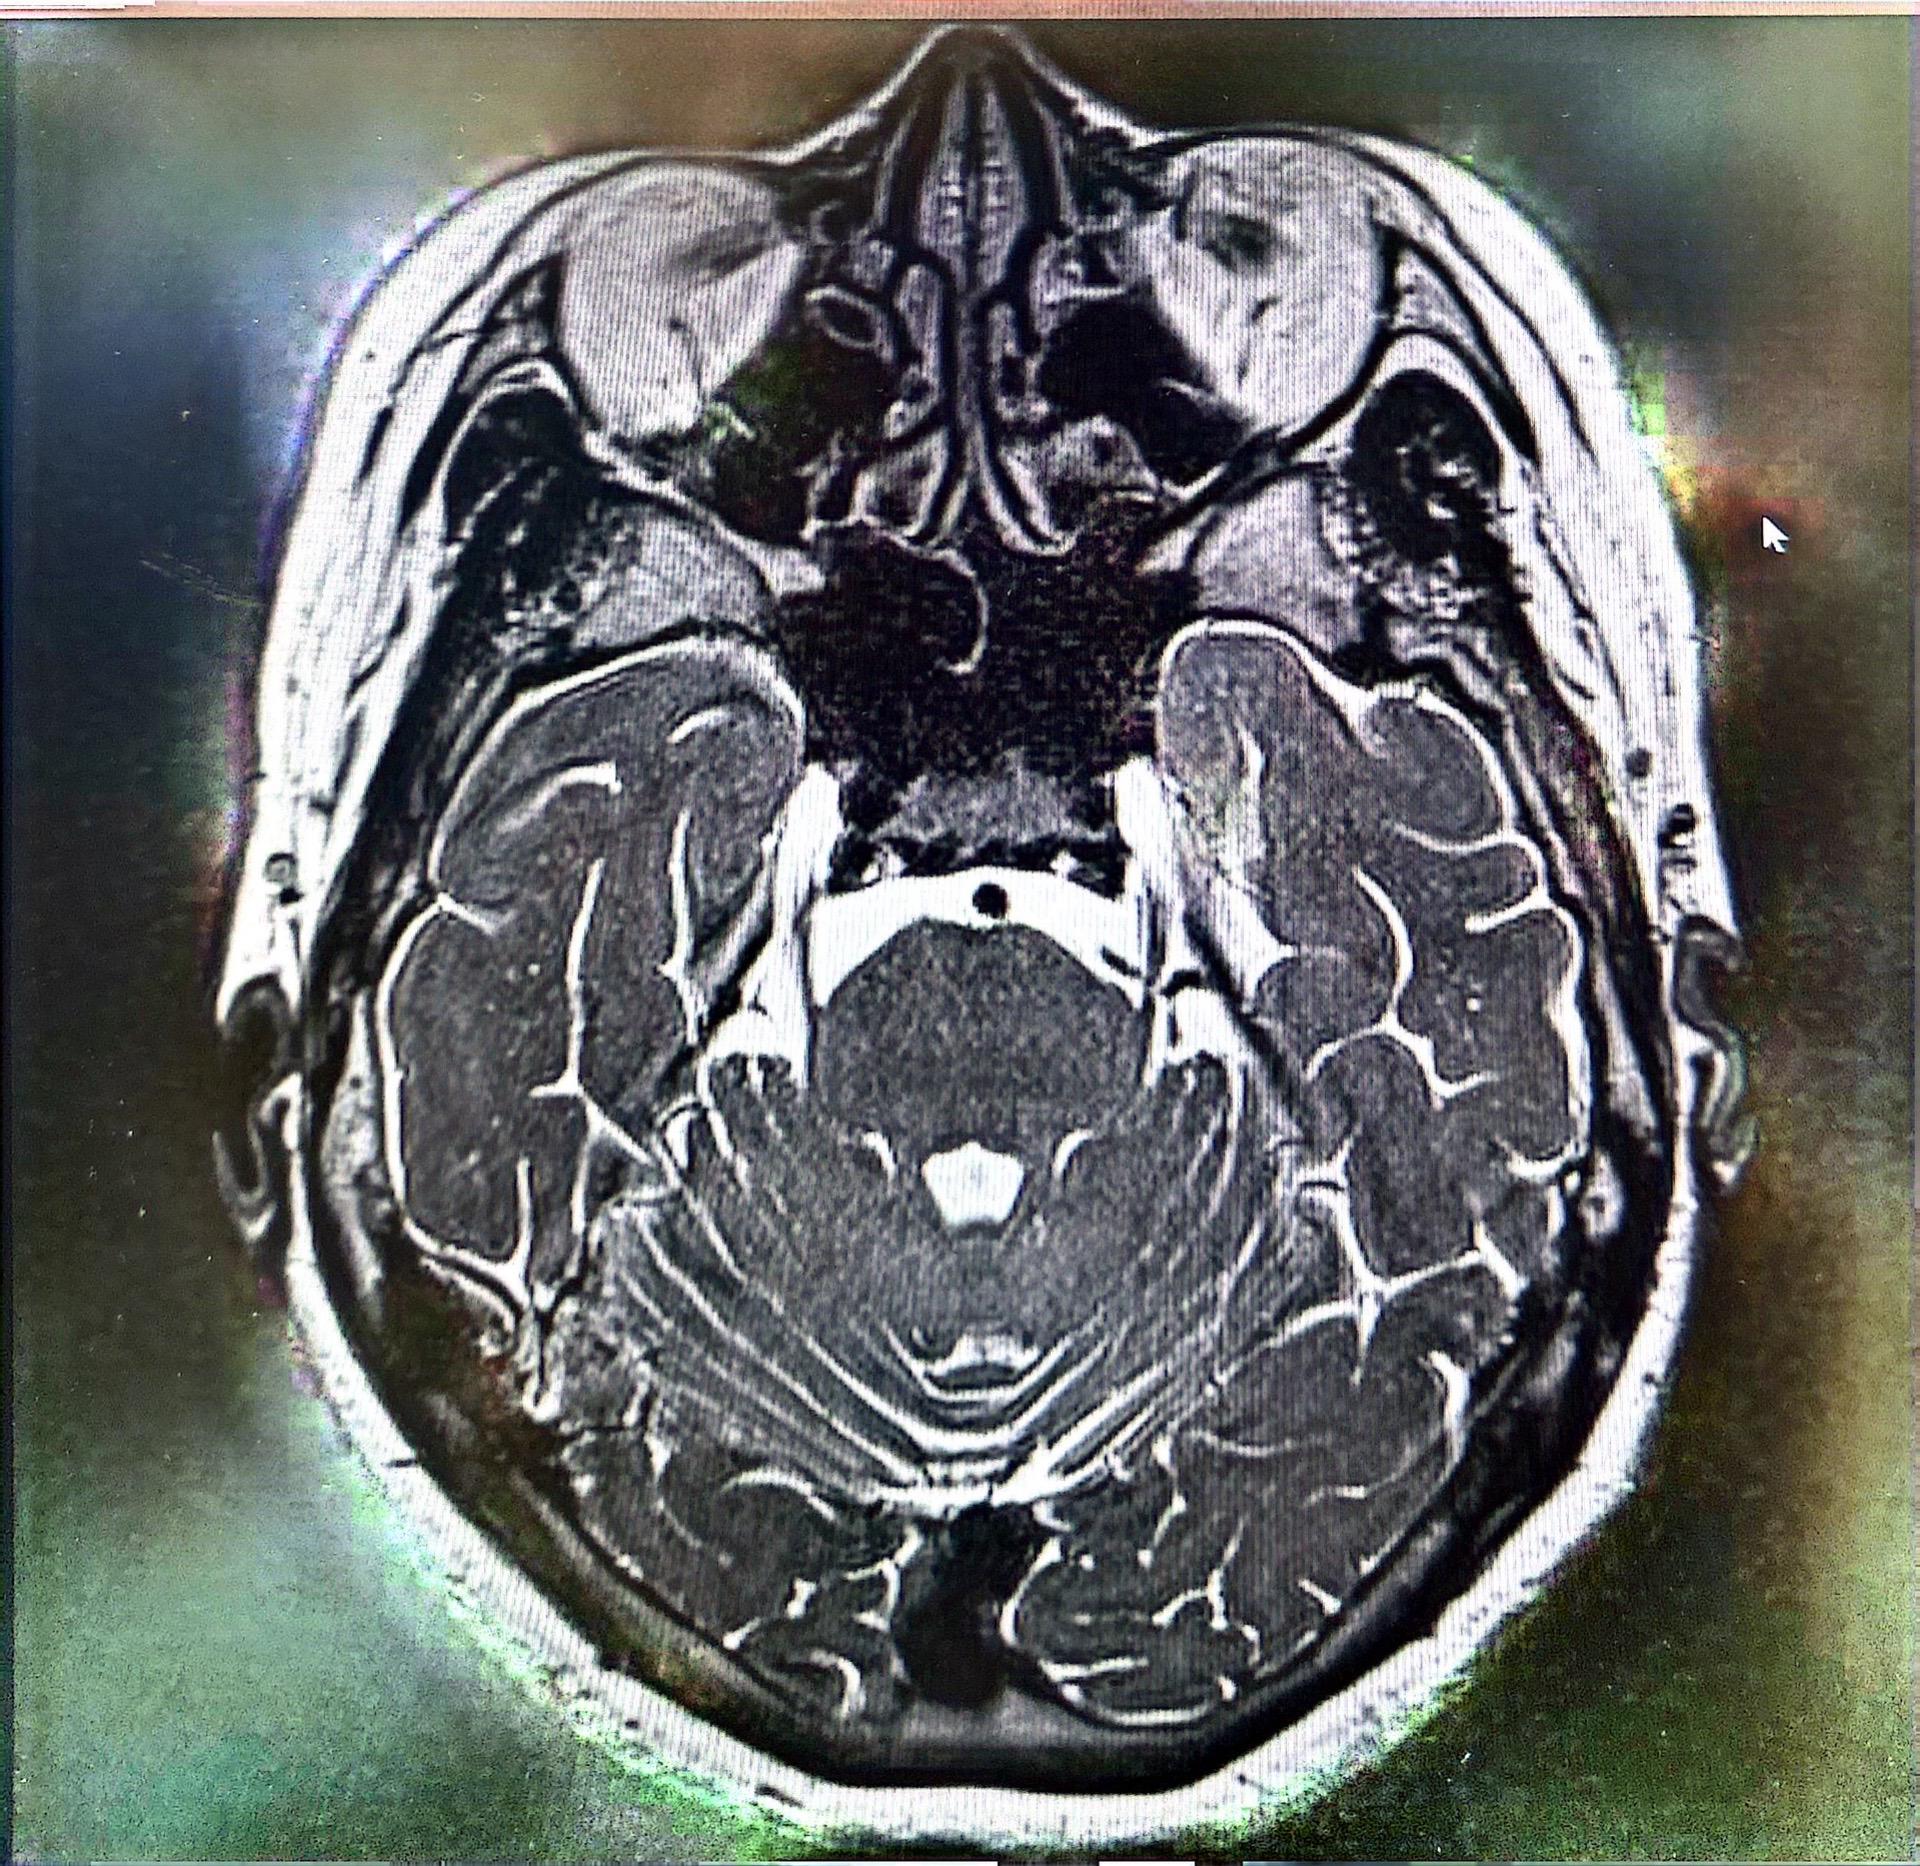

三台手术完成。今天紧凑了一点,一台脑起搏器植入治疗帕金森病,一台三叉神经痛减压,一台三叉神经痛球囊压迫术